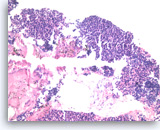

Solid pseudopapillary tumor,

Pancreas FNA, Cell Block.

The tumor shows pseudopapillae with hyalinized fibrovascular cores lined by several layers of bland epithelioid cells.

20X

Solid pseudopapillary tumor,

Pancreas FNA, Cell Block.

The tumor shows pseudopapillae with hyalinized fibrovascular cores lined by several layers of bland epithelioid cells.

20X